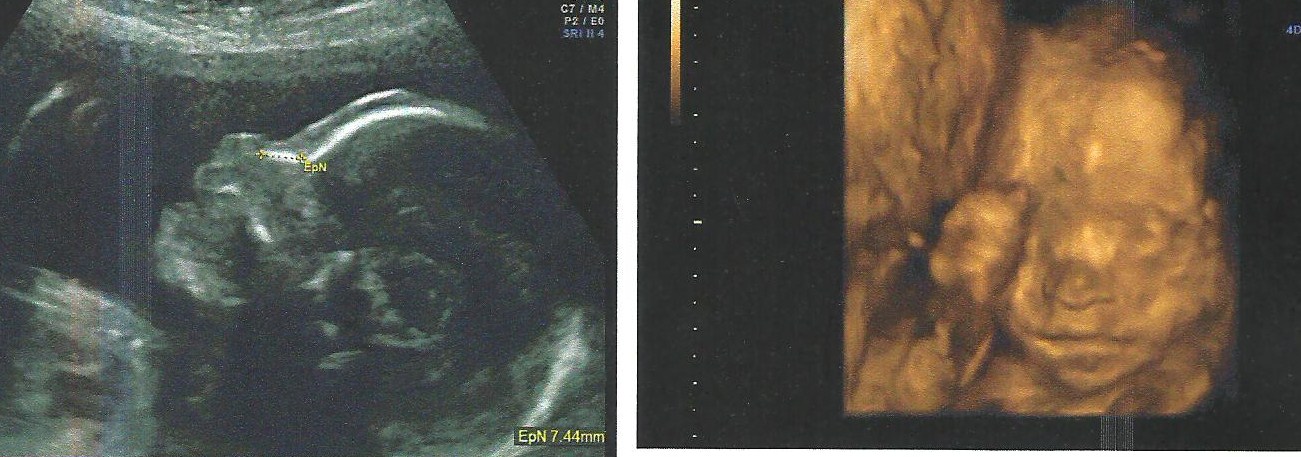

Anything else you can post to guess on? Skull? Nub? Xx

Attachment 18003

I can't guess based on the first pics but beautiful baby!!